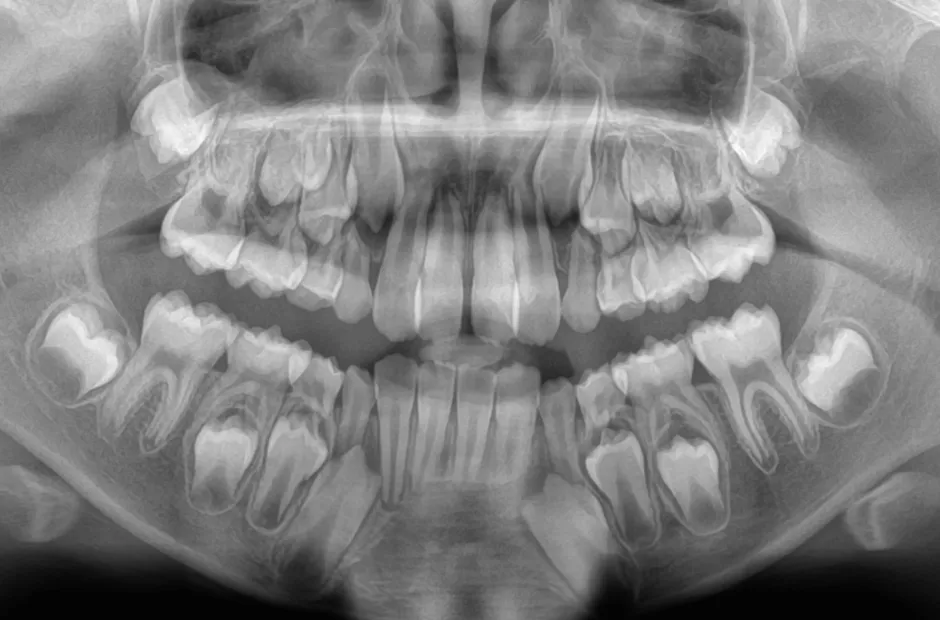

口腔内写真やレントゲンの撮影、歯型取りなど、口や顎の状態を詳しく把握するための精密検査を行ないます。さらに、骨の成長状況や身長・体重の増加傾向、永久歯の生えかわりについても確認します。

永久歯が生えてこない(埋伏歯)

何らかの原因で永久歯が正常に生えることができず、歯肉に埋もれたままになる歯のことを埋伏歯といいます。この歯を放置すると、隣の歯根を吸収してしまうことがあるため、早めの治療が必要です。埋伏歯を早期に発見できると、抜歯せずに矯正治療で正常な位置に戻せる可能性が高くなります。これは、小児矯正では、顎の成長を促進して歯が正しく並ぶスペースを作ることができるからです。そのため、乳歯が永久歯に生え変わり始めるころに一度受診し、埋伏歯の有無を確認することが大切です。

埋伏歯がある場合は、矯正装置を使って歯列を拡げ、必要に応じて開窓術や牽引を行なって埋もれた歯を正しい位置に引き上げます。すでに永久歯が生えそろっていても、適切な治療を受けることで抜歯せずに改善できる場合もあるので、気になることがあれば早めにご相談ください。

3歯以上埋伏歯がある場合は、矯正治療が保険適用になります。